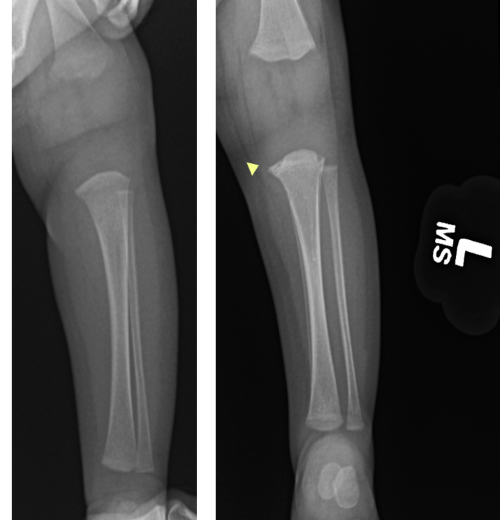

Image 4. Frontal view of left tibia and fibula. A. Normal. B. Follow up. Irregularity of proximal tibial metaphysis, concern for healing classic metaphyseal lesion